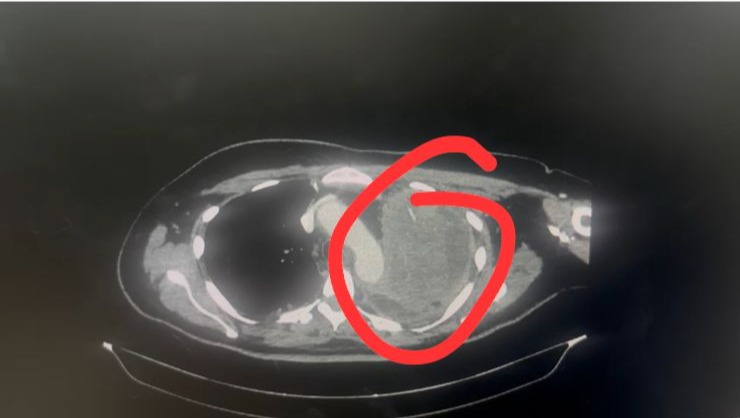

On Thursday September 14th they did another CT & found a large tumor that is taking up nearly her entire left lung.

The tumor is very very large, as you can see in the photo attached below it takes up the whole lung and is starting to push against other structures and organs. Obviously this is not ideal and needs to be dealt with as soon as possible.